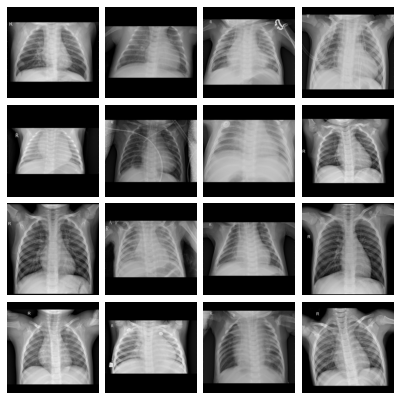

- pneumonia, Pediatric Pneumonia:

-

Dataset of pediatric chest X-ray images labeled for pneumonia classification, derived from [kermany_identifying_2018]. The 5,856 original images were zero-padded to a square shape and resized to pixels using bi-cubic interpolation (some images were up-scaled); the 283 images that were originally in RGB format were converted to grayscale. From the original annotations, we derived a binary classification task for pneumonia presence as well as a multi-class task differentiating between normal images, bacterial pneumonia and viral pneumonia.